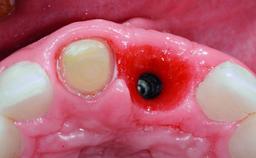

A 32-year-old female Caucasian patient with a compromised maxillary right central incisor was referred to us by a general dentist. Her chief complaints were discomfort and mobility of tooth 11 with unsatisfactory esthetics due to discoloration. The patient reported a previous trauma, some years earlier, as the origin of pathology on the afflicted tooth. Anamnesis was negative for any other dental or periodontal pathology in the remaining dentition. The patient did not take any medication and reported to be a light smoker (5–10 cigs/day). She had high esthetic expectations of her treatment. The extraoral examination revealed a high smile line with full exposure of her maxillary teeth and surrounding soft tissue in the area between the second premolars.

Case Type Single-Tooth Space

Jaw Maxilla

Area Anterior

# of Teeth 1

# of Implants 1

Bone Volume Deficient horizontally, requiring prior grafting

Esthetic Risk High